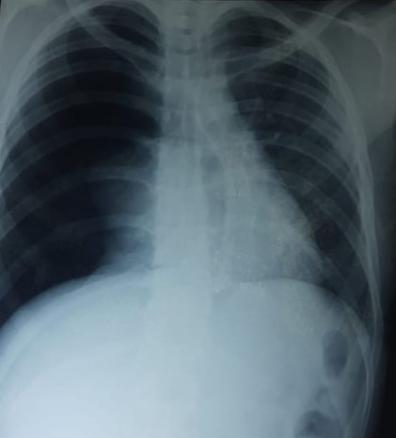

Radiographie thoracique de face avec une hyperclarté homogène, sans trame vasculaire, limitée en dedans par le moignon pulmonaire.